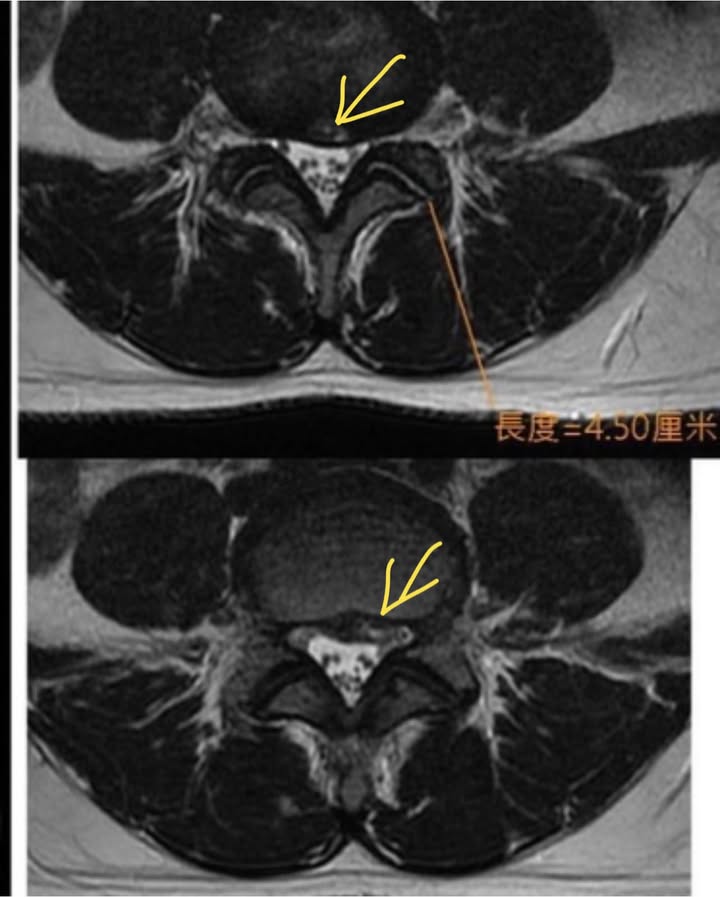

2.左側L4L5椎間盤突出

❗️術前溝通:片子上看起來突出只有一點,且患者沒有大小便失禁的症狀,也沒有大小便疼痛,也沒有垂足跟腳萎縮情況,估計脊髓沒損傷,只是突出的椎間盤壓迫神經根導致,安排三週治療看效果如何,如果有改善就繼續治療,如果還是麻痛到不行就建議開刀